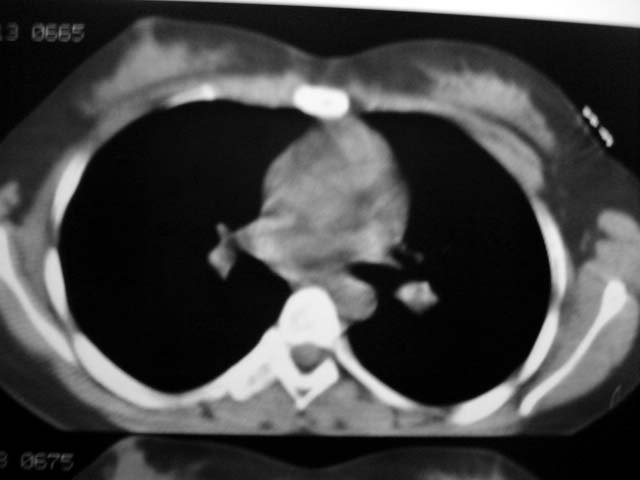

标题: CT12463:女,19岁,炎性假瘤?结核球? [打印本页]

女,19岁,体检时发现。炎性假瘤?结核球?

早产儿,幼时体弱,常感冒肺部感染,13岁后好转。两月前“感冒”后咳嗽两周。

纵隔窗肿块明显较肺窗小,切粗长毛刺,“倒核桃”征:考虑炎性假瘤

考虑炎症,抗炎后复查。理由:病变肺窗显示的大小明显大于纵隔窗,提示病变周围为密度偏低的渗出改变。不同于结核球和肿瘤。